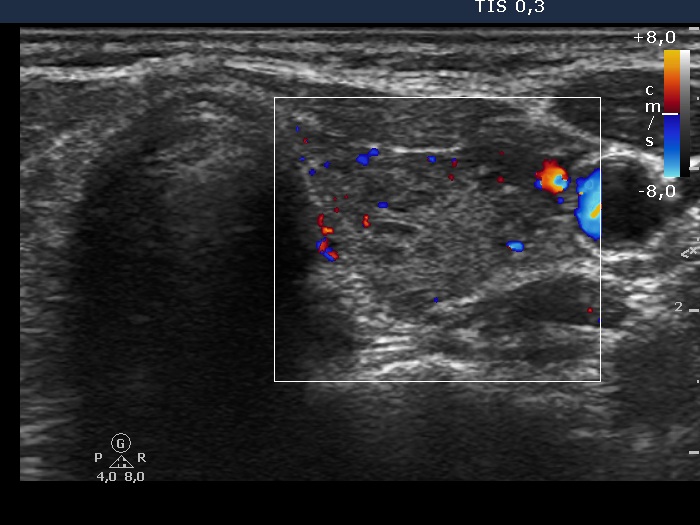

Ultrasonography: the thyroid was echonormal with many hypoechogenic areas of various sizes. The echogenicity index was around 30%. We found no suspicious lesions, the hypoechogenic area in question was located in the ventrolateral part of the thyroid. None of the hypoechogenic areas fit nodule, these were in fact more active foci of lymphocytic thyroiditis.

Comment: the presence of multinucleated giant cells in the case of a thyroiditis argue for de Quervain's thyroiditis. Nevertheless, the ultrasound pattern including the normal vascularization excluded this possibility.